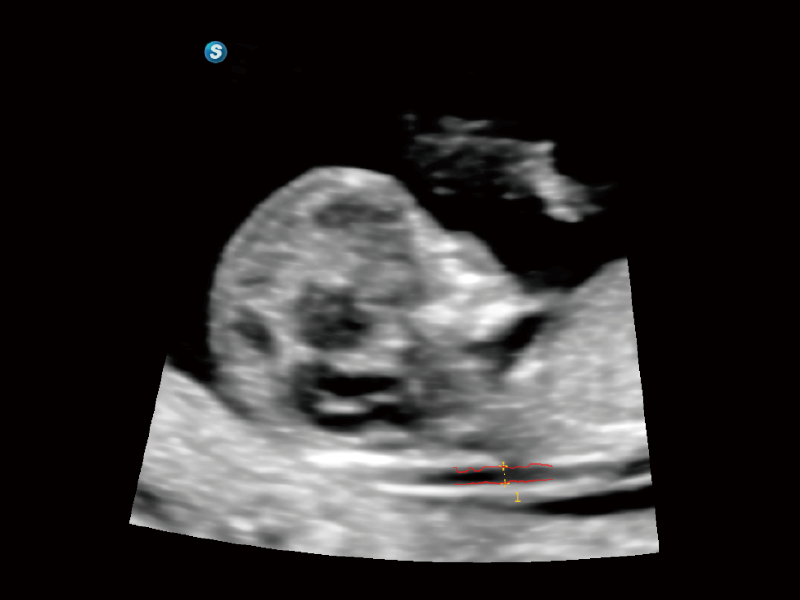

作为开立医疗全新打造的超高端旗舰超声产品,从探头抬起唤醒开启扫查到多维探头发射接收,通过先进的场成像发射、自适应聚合重建等技术,基于RF Data原始射频数据在图像生成、高端功能等方面实现突破,为妇产科、儿科提供全方位临床解决方案。

独有场成像发射技术

自适应聚合重建技术

独家XPUs混合硬件架构